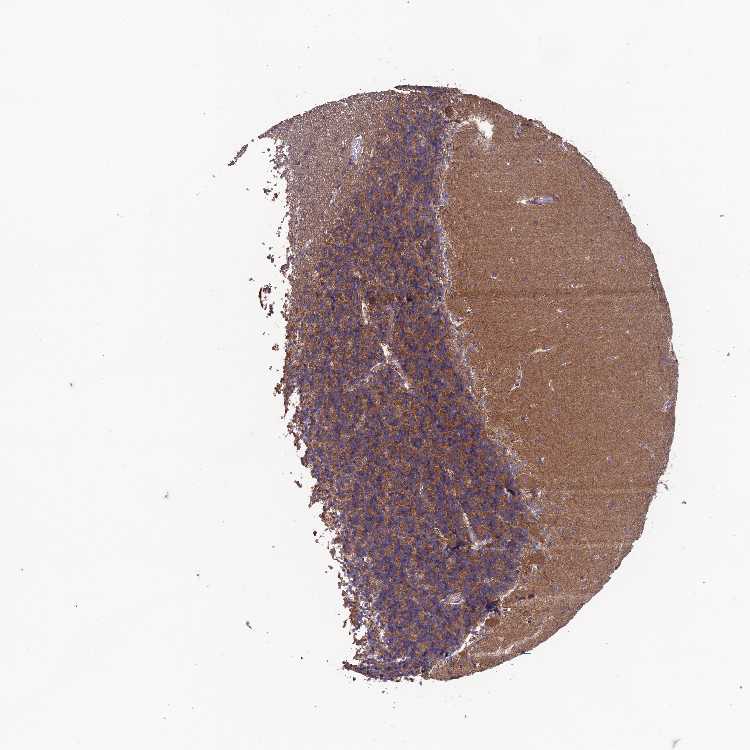

CEREBELLUM - Antibody stainingi

Antibody staining in the annotated cell types in the current human tissue is reported as not detected, low, medium, or high, based on conventional immunohistochemistry profiling in selected tissues. This score is based on the combination of the staining intensity and fraction of stained cells.

Each image is clickable and will lead to virtual microscopy that enables deeper exploration of all samples and also displays staining intensity scores, fraction scores and subcellular localization as well as patient and tissue information for each sample.

Antibody HPA042295

Purkinje cells Medium

Cells in granular layer High

Cells in molecular layer Not detected